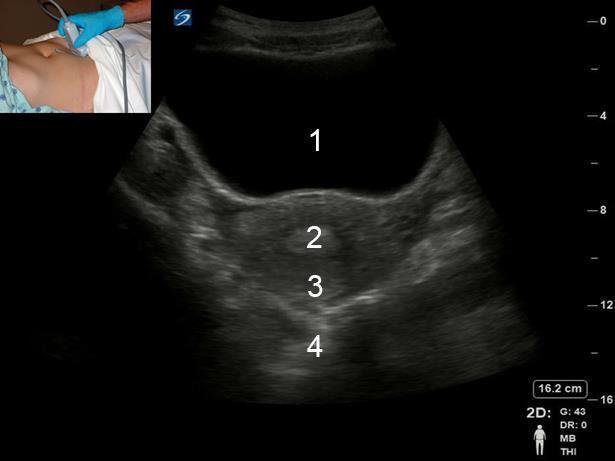

Pelvic Transabdominal (TA) Transverse Uterus Image

膀胱

子宮内膜

子宮

後部盲管